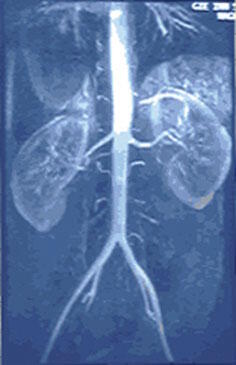

Des maladies des reins sont fréquentes chez les patients diabétiques. Quatorze anciens combattants avec un diabète de type II avancé ont eu leur alimentation supplémentée avec un isolat de protéine de soja ou avec de la caséine de lait pendant deux périodes de traitement de huit semaines dans le cadre d'une étude qui a duré sept mois. Les quantités de protéines données à chaque patient ont été calculées en fonction de leur poids. Des échantillons d'urine et de sang ont été collectés au début et à la fin de l'étude. |

Les chercheurs ont commenté cette étude en disant que ces résultats suggéraient qu'une modification alimentaire aussi simple à mettre en œuvre que de consommer des aliments riches en soja pourrait aider à prévenir les maladies rénales diabétiques en plus d'améliorer le profil lipidique. |